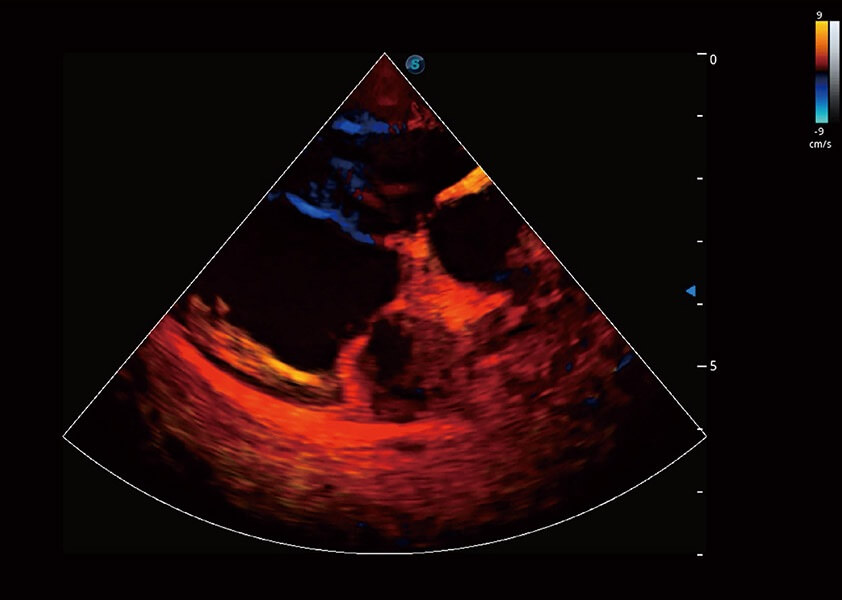

ProPet 60 作为一款高端台式动物超声设备,为动物医生的日常诊断提供了一系列贴合动物临床需求、解决临床实际问题的高级成像功能。凭借全系列高清探头,满足医生对腹部、心脏、生殖、浅表、肌骨等成像的所有需求,切实帮助您提升检查效率,提高诊断信心。

兽用彩色多普勒超声诊断系统

动物是人类最亲密的朋友和最值得信赖的伙伴。百老汇电子游戏官网也一直致力于探索动物专用的超声影像解决方案。 全新推出的ProPet系列,是百老汇电子游戏官网在动物超声影像智能化、专业化、精准化的一次跨越式革新。动物不能用言语来表述自己的不适,通过超声影像,ProPet系列搭建了动物医生与不同物种沟通的“桥梁”,为动物医生注入了“治愈之力”。